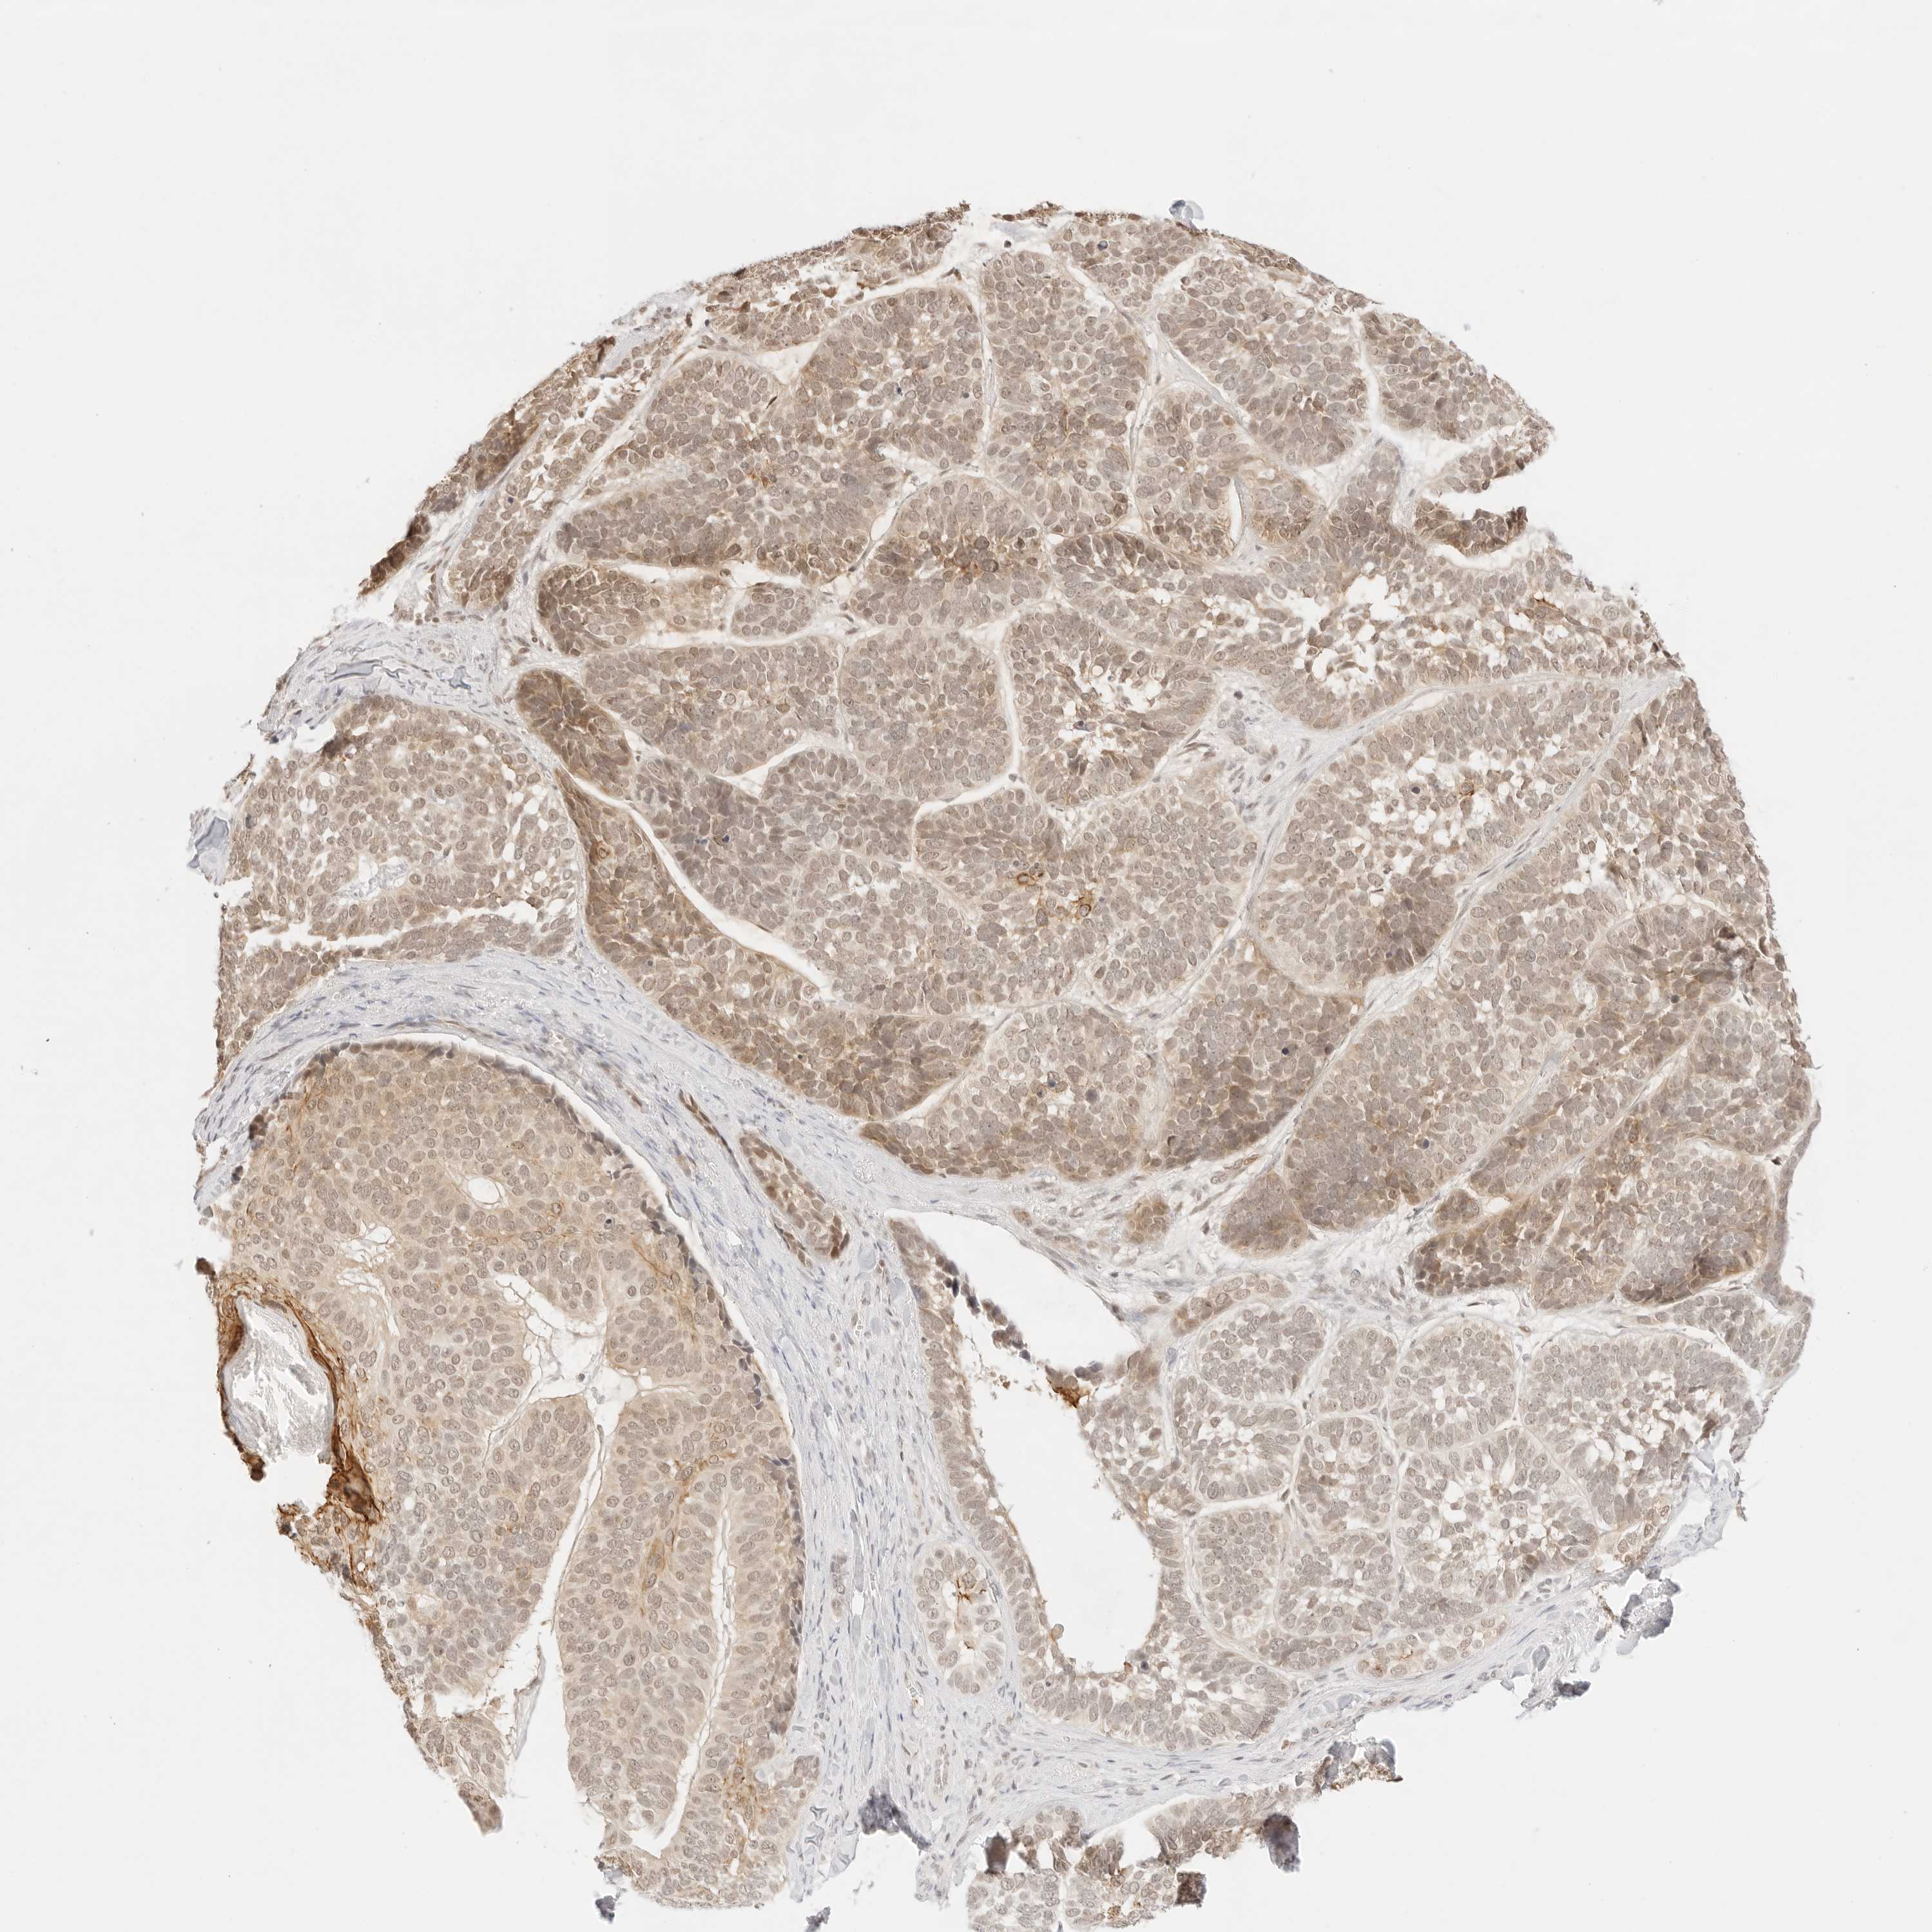

SKIN CANCER - Protein expressioni

A mouse-over function shows sample information and annotation data. Click on an image to view it in a full screen mode. Samples can be filtered based on level of antibody staining by selecting one or several of the following categories: high, medium, low and not detected. The assay and annotation is described here.

Each image is clickable and will lead to virtual microscopy that enables deeper exploration of all samples and also displays staining intensity scores, fraction scores and subcellular localization as well as patient and tissue information for each sample.

Antibody HPA018122

Staining

High

Medium

Low

Not detected

Intensity

Strong

Moderate

Weak

Negative

Quantity

>75%

75%-25%

<25%

None

Location

Nuclear

Cytoplasmic/membranous

Cytoplasmic/membranous,nuclear

Basal cell carcinoma